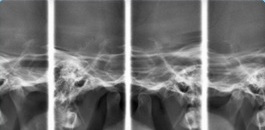

Radiografia digital das ATMs

Visualização de forma planográfica das ATMs, com boca aberta e fechada.